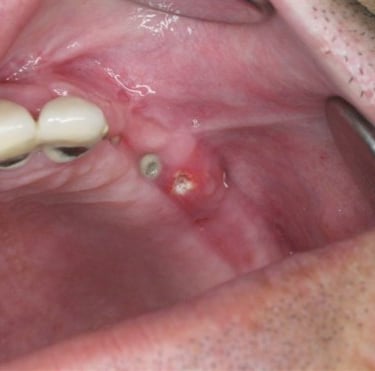

Infección postoperatoria

La infección postoperatoria es una complicación que puede ocurrir después de la colocación de un implante dental, manifestándose con dolor, hinchazón y fiebre.

Los pacientes deben estar atentos a signos de infección después de la cirugía.

El tratamiento incluye antibióticos y, en algunos casos, la limpieza quirúrgica del área afectada.